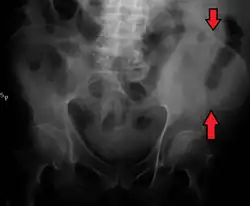

The crest of the ilium (or iliac crest) is the superior border of the wing of ilium and the superolateral margin of the greater pelvis.

The iliac crest stretches posteriorly from the anterior superior iliac spine (ASIS) to the posterior superior iliac spine (PSIS). Behind the ASIS, it divides into an outer and inner lip separated by the intermediate zone. The outer lip bulges laterally into the iliac tubercle.[1] Palpable in its entire length, the crest is convex superiorly but is sinuously curved, being concave inward in front, concave outward behind.[2]

The top of the iliac crests also marks the level of the fourth lumbar vertebral body (L4), above or below which lumbar puncture may be performed. Furthermore, said level is often referred to as the "intercristal line".

Iliac crest labeled at center right

Iliac crest